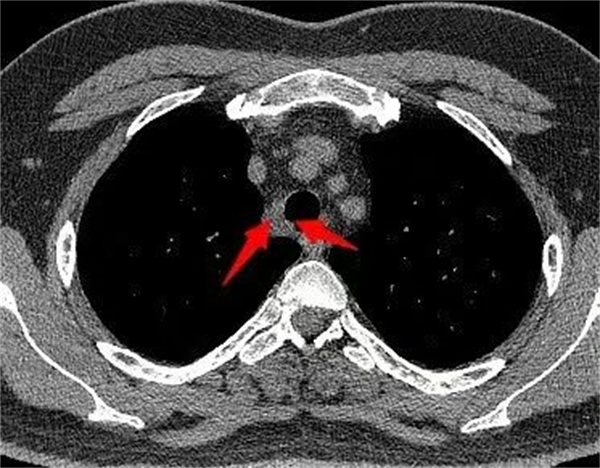

患者为35岁男性,在体检中发现上纵隔气管旁存在一直径约1.5厘米的肿物。胸外科为其进行了超声支气管镜引导下经支气管针吸活检术,病理结果提示为神经鞘瘤。影像学检查显示肿物疑似侵犯气管,但气管镜观察见局部黏膜尚光滑、仅略有隆起,病情具有一定复杂性。

手术在胸腔镜下进行。术中探查发现,尽管肿物对气管形成局部压迫,但未侵犯气管壁。在团队密切配合下,手术顺利完成肿瘤完整切除。术后病理结果进一步证实为神经鞘瘤。患者术后恢复顺利,第二天拔除胸腔引流管,第四天出院。